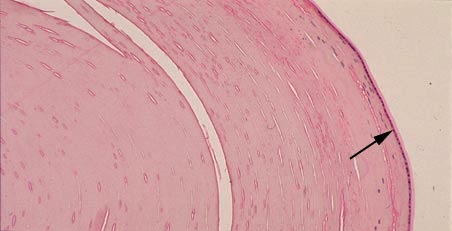

IX-28G Lens. In this micrograph the lens fibers can be seen. Note the anterior cuboidal epithelium (arrow) which is covered by a lens capsule on its surface.